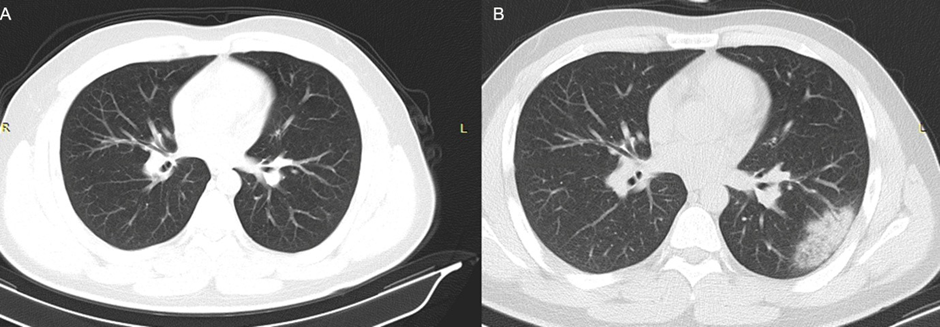

The data of visually negative CT scan were transferred to an offline workstation, and semi-automated parenchyma volume segmentation and fully automatic volumetric density calculations were performed using dedicated software (3D Slicer v4.10.2 software, http://www. slicer.org). The lung lobe to be segmented was determined based on the positive finding at second CT scan (Figure 2 A and B). Three radiologists with 10 years of experience in thoracoabdominal radiology processed the data retrospectively and a consensus was reached. Lung segmentation was performed in two steps: First, a threshold function was applied and parenchyma with density between -500 and -1024 HU was selected (Figure 3A). This selection was used as masking, and then semiautomated tracing function was applied to each slice for the selection of the symmetric lung lobes separately (Figure 3B). While the level tracing method enabled the segmentation of the lung, the threshold function eliminated the pixels with high density from anatomical structures, such as vessels and bronchi. Volumetric density calculations were performed automatically for each lobe using the built-in segmentation statistics of the software.

Figure 2: Consecutive CT scans of a 25-year-old male patient performed at an interval of five days. The first CT (A) was negative whereas the second CT (B) showed focal consolidation with surrounding ground-glass opacities.